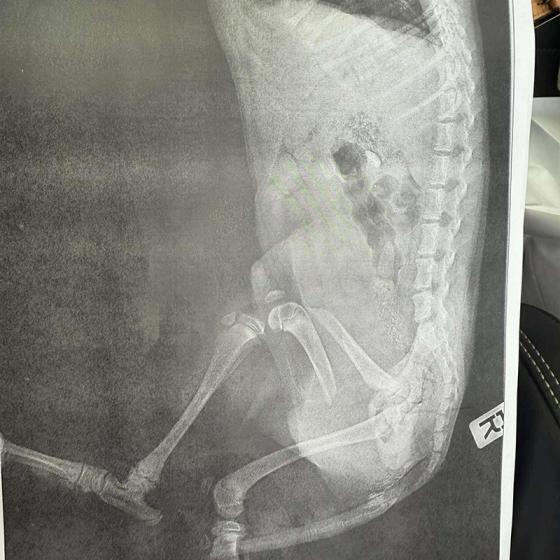

Drobec, ktorý medzičasom dostal meno Gerro, sa napriek všetkému celý čas tešil ľudskej pozornosti a krútil chvostíkom. Má veľmi škaredé zlomeniny prednej aj zadnej labky, pomliaždeniny na celom telíčku, ale našťastie lebka a chrbtica by mali byť v poriadku. Naše srdcia sú z tohto prípadu dolámané tiež na milión kusov, modlíme sa a veríme, že operácie zvládne! My budeme pri ňom a pomôžeme mu vo všetkom, v čom len bude treba.

Momentálne je hospitalizovaný u nášho veterinára, kde ho včera pripravovali na náročné operácie, ktoré by podľa plánov mal podstúpiť dnes. Čaká ho ešte veľmi dlhá cesta, ale pomôžeme mu zvládnuť každý jeden krôčik!